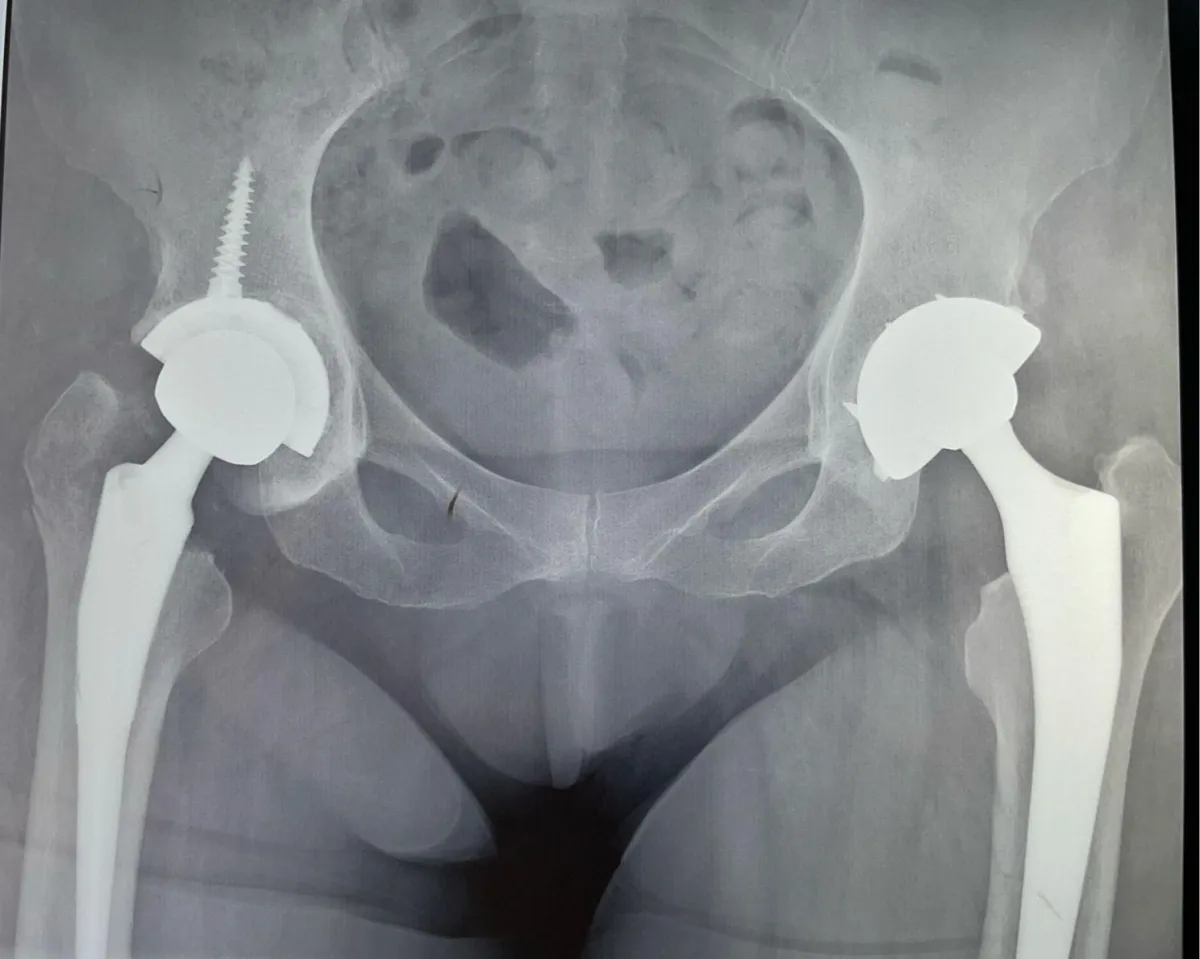

Casos Clínicos

Procedimientos representativos de nuestra práctica en cirugía de cadera, fracturas y prótesis articulares.